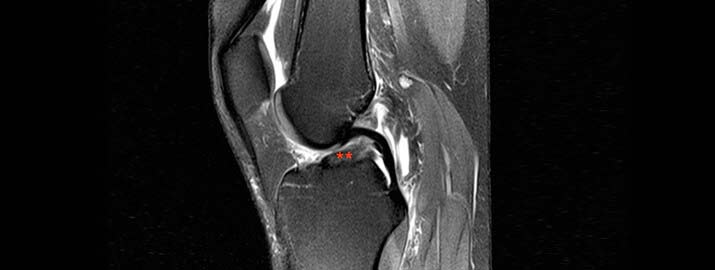

Imagen de resonancia con el LCA roto